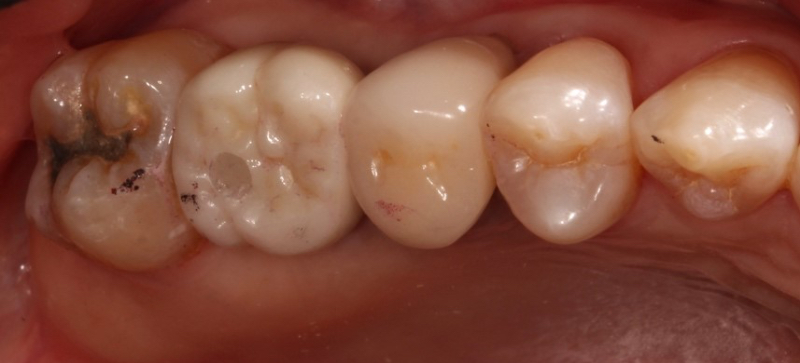

However, cement-retained implant crowns can present challenges if cement is not effectively removed. This is especially true for prefabricated abutments, where the margins can be millimeters subgingival. Multiple studies have demonstrated that patients with cement-retained implant crowns with excess cement are at a higher risk of developing peri-implantitis.

Dr. Chandur Wadhwani, a Seattle-area prosthodontist, demonstrated how excess implant cement can lead to inflammation around implants, contributing to bone loss and peri-implantitis3. As a result, it is advised to design implant crown margins to remove excess cement and take a post-cementation radiograph to determine if excess cement remains after delivering a cement-retained implant crown.

Dr. Georgios Kotsakis, a University of Texas Health Science Center School of Dentistry faculty member, suggests designing implant crown margins that do not extend more than 1.0 mm subgingivally and considering using zinc oxide eugenol or zinc phosphate cement rather than a resin-based cement. Resin-based cements may experience greater biofilm accumulation than zinc oxide eugenol or zinc phosphate cements, leading to a significant risk of inflammation around the implant restoration2.